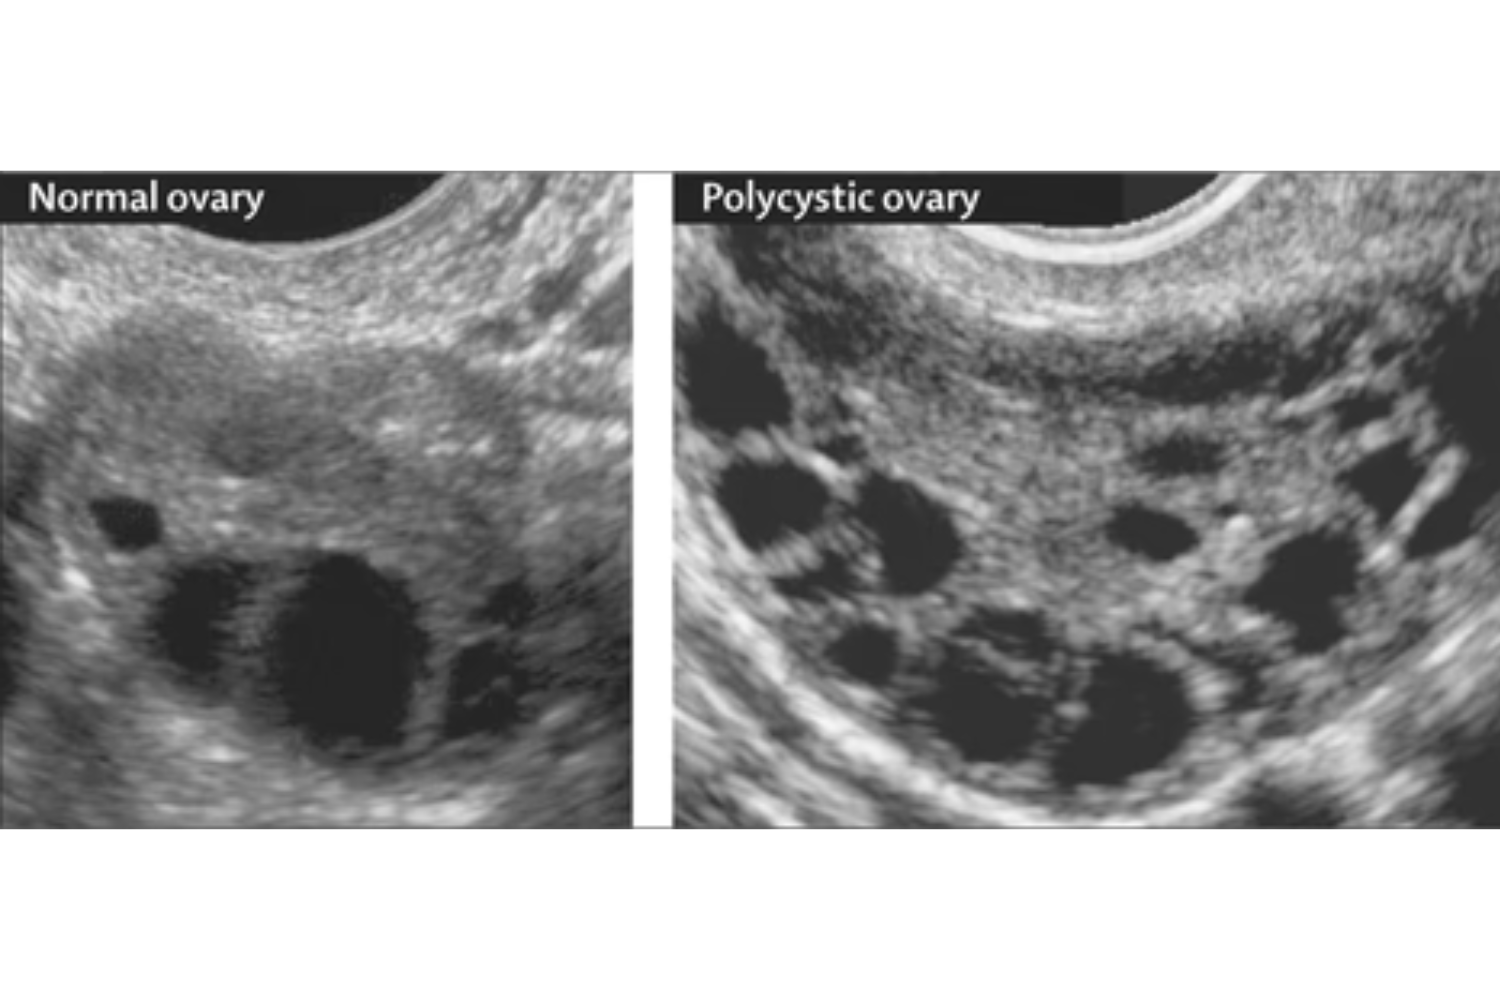

Amélioration du diagnostic moléculaire du SOPK, en complément des critères cliniques et échographiques.